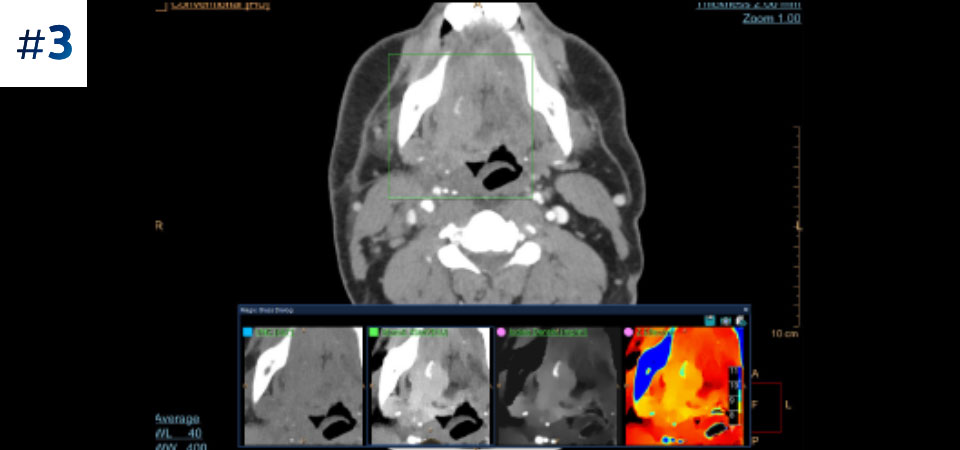

Опухоль в области шеи